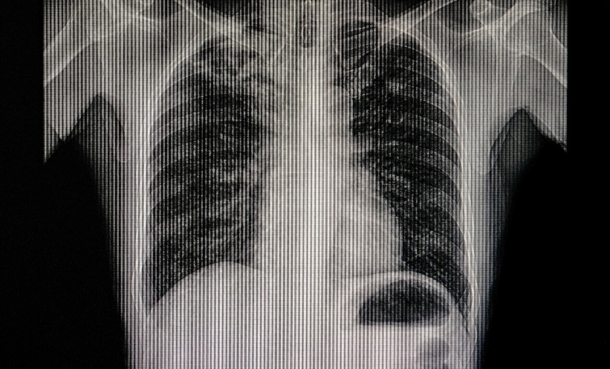

Early Health Technology Assessment to Detect Incidental Pulmonary Embolisms on CT